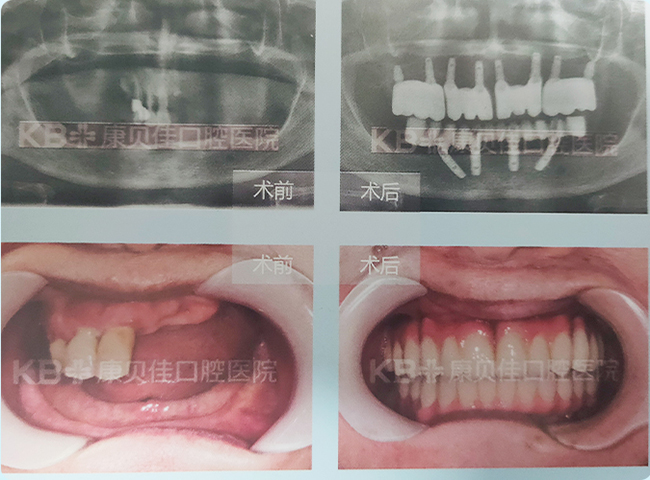

赵先生 70岁

因牙周炎致牙齿松动,拔除,全口种植,期间活动义齿过渡修复,半年后完成永久性修复。

治疗方案:

上颌种植2颗恢复3颗 下颌种植6颗恢复半口